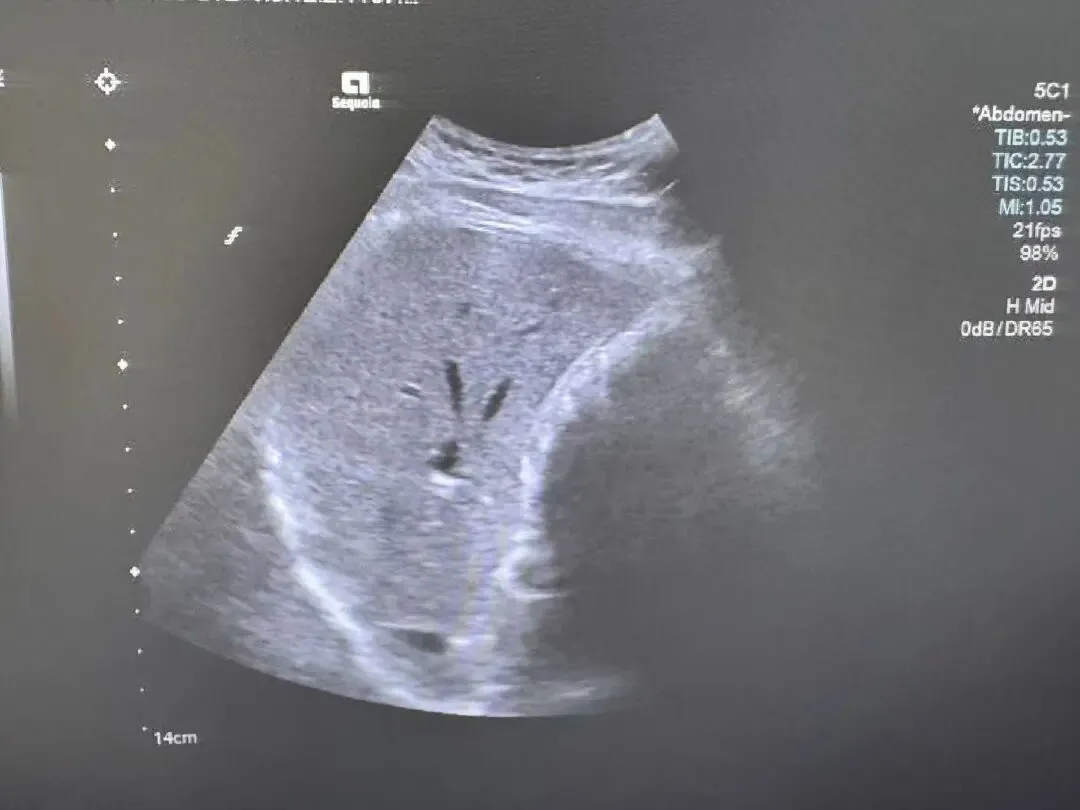

胆囊璧内结石

胆囊壁稍毛糙,壁内可见微小强回声斑,后方出现多重反射回声,类似彗星尾征。